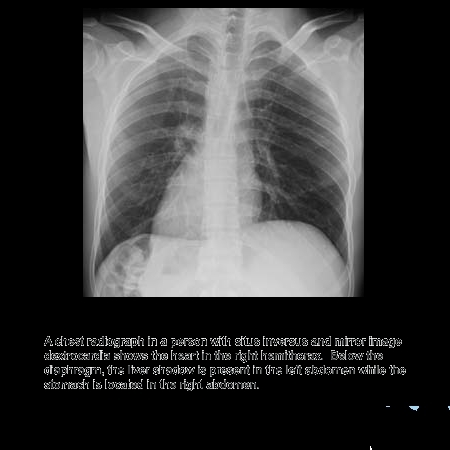

Dextrocardia Situs Inversus

and the diaphragm is higher on the right side....either wrong placed xray or situs inversus

yaaa gud pic,can c the apex of heart facing right side....